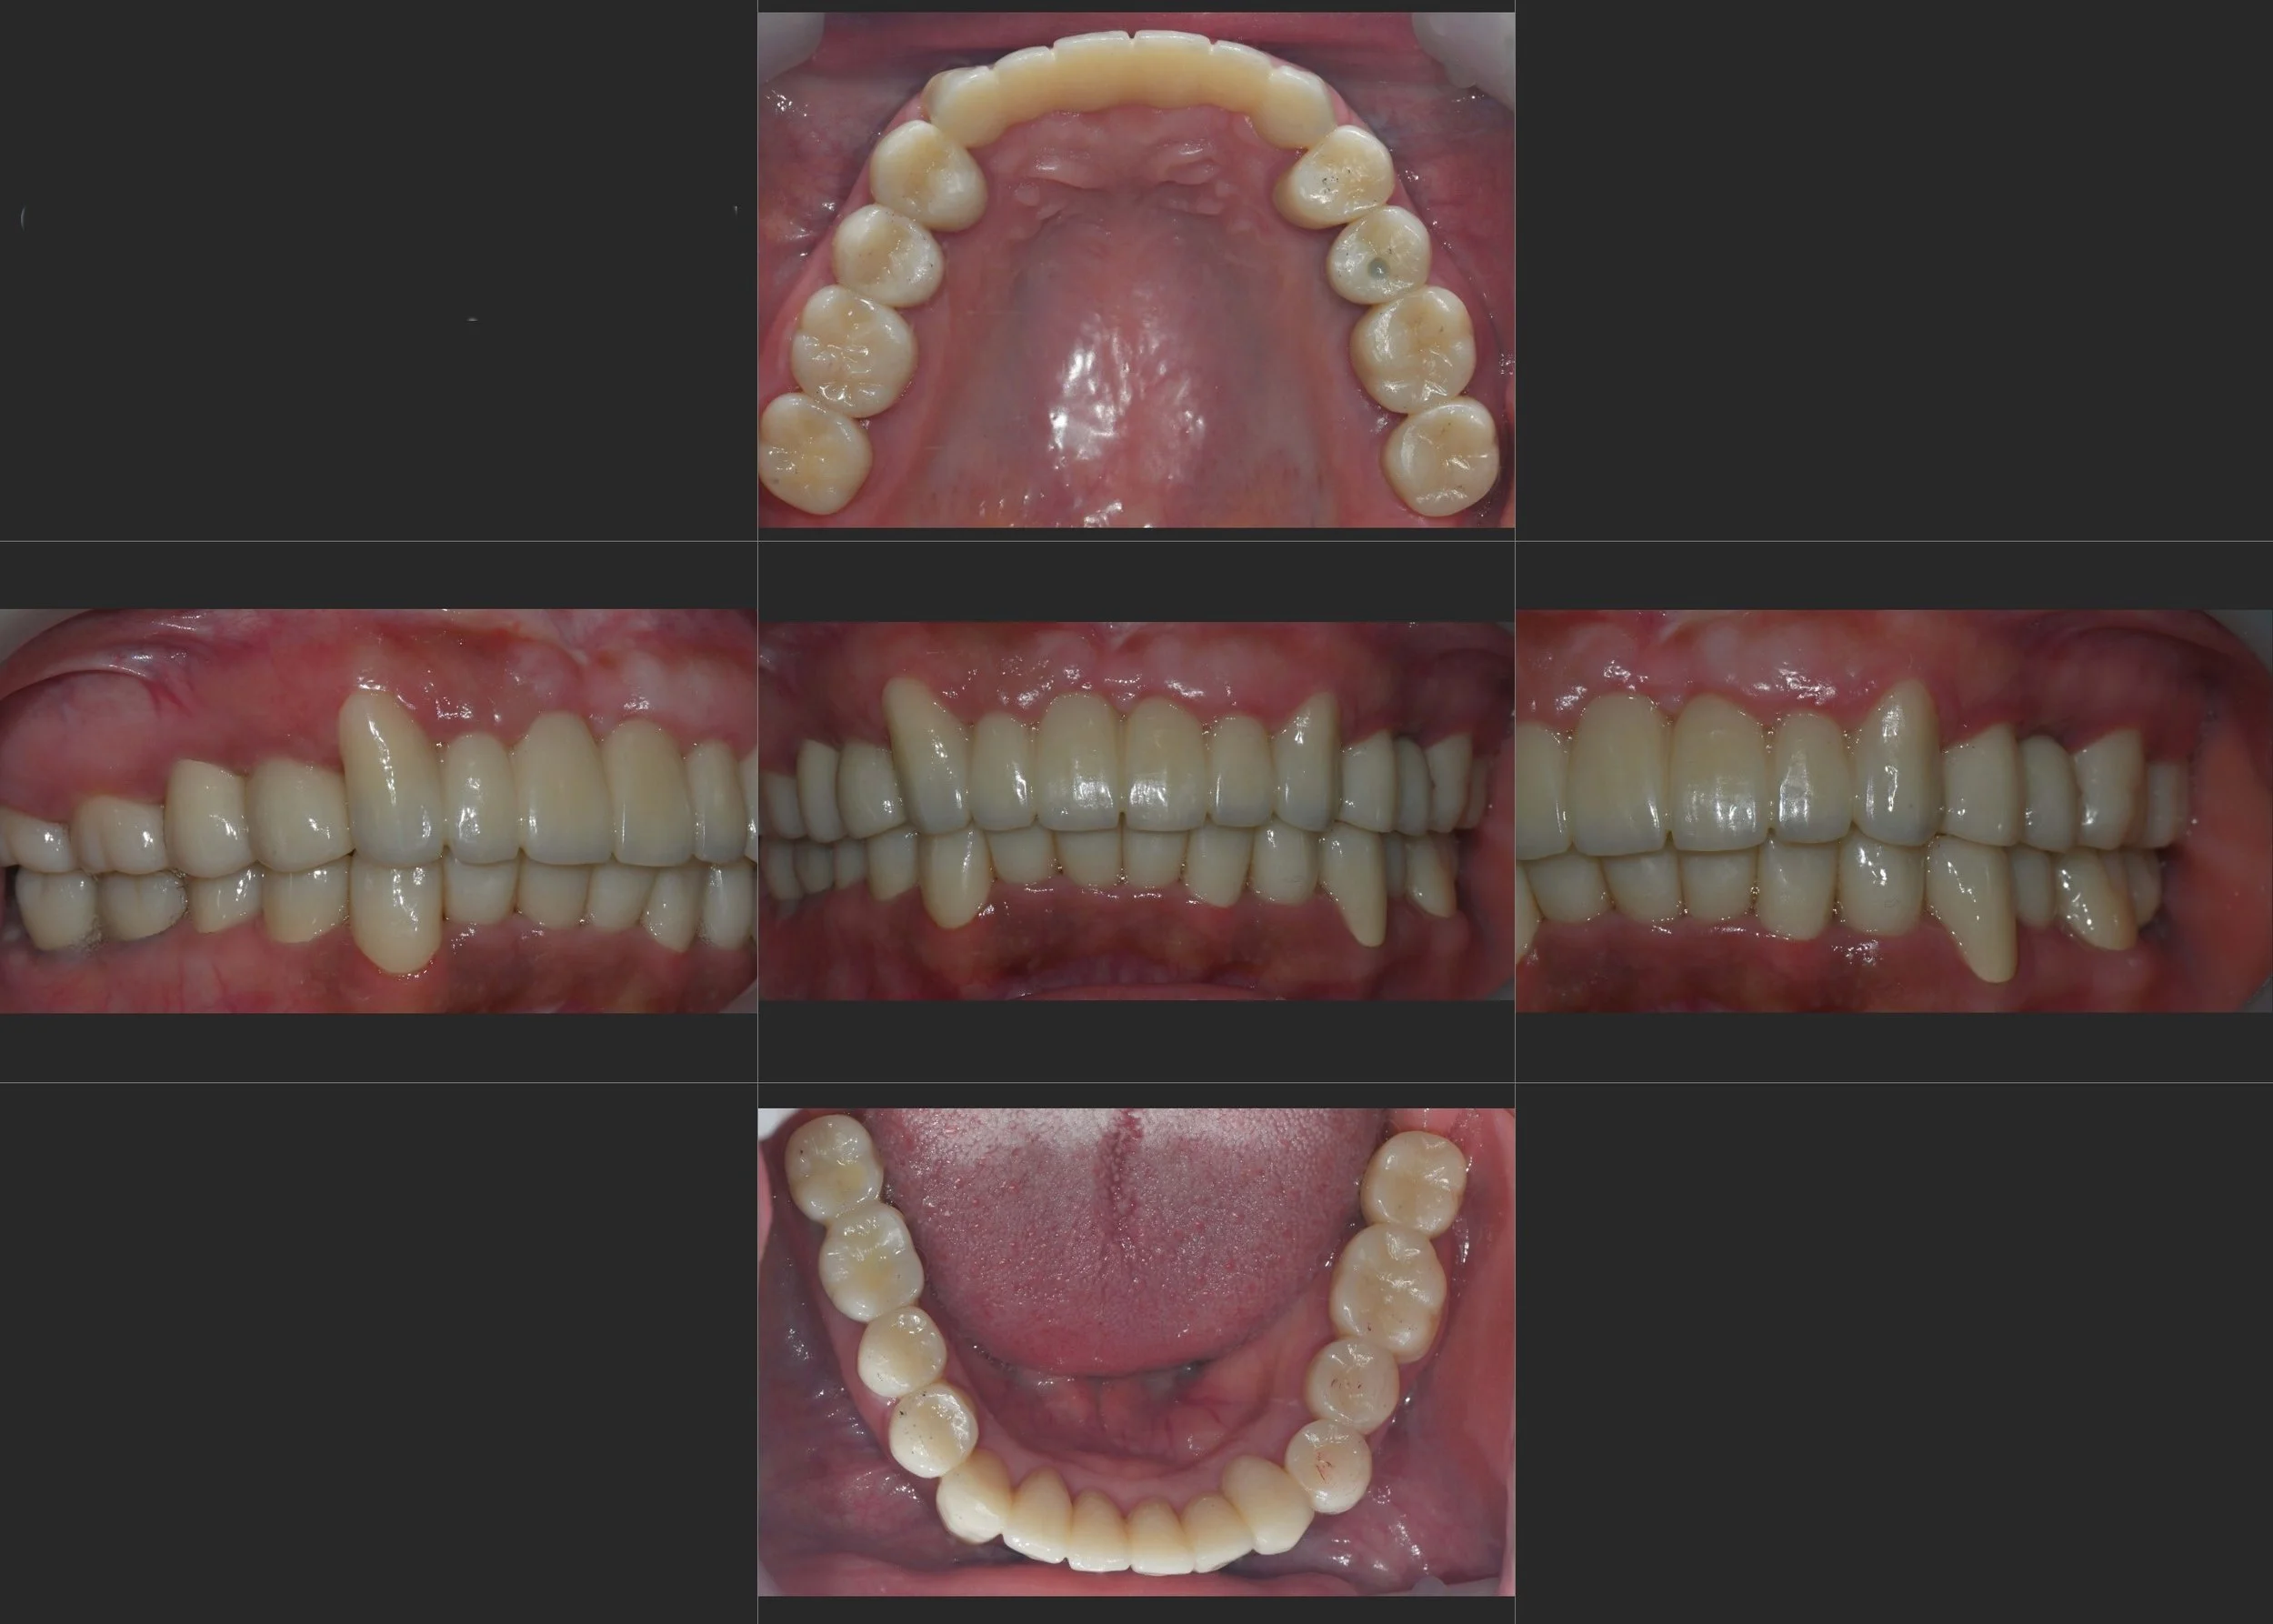

INTRA ORAL - AFTER